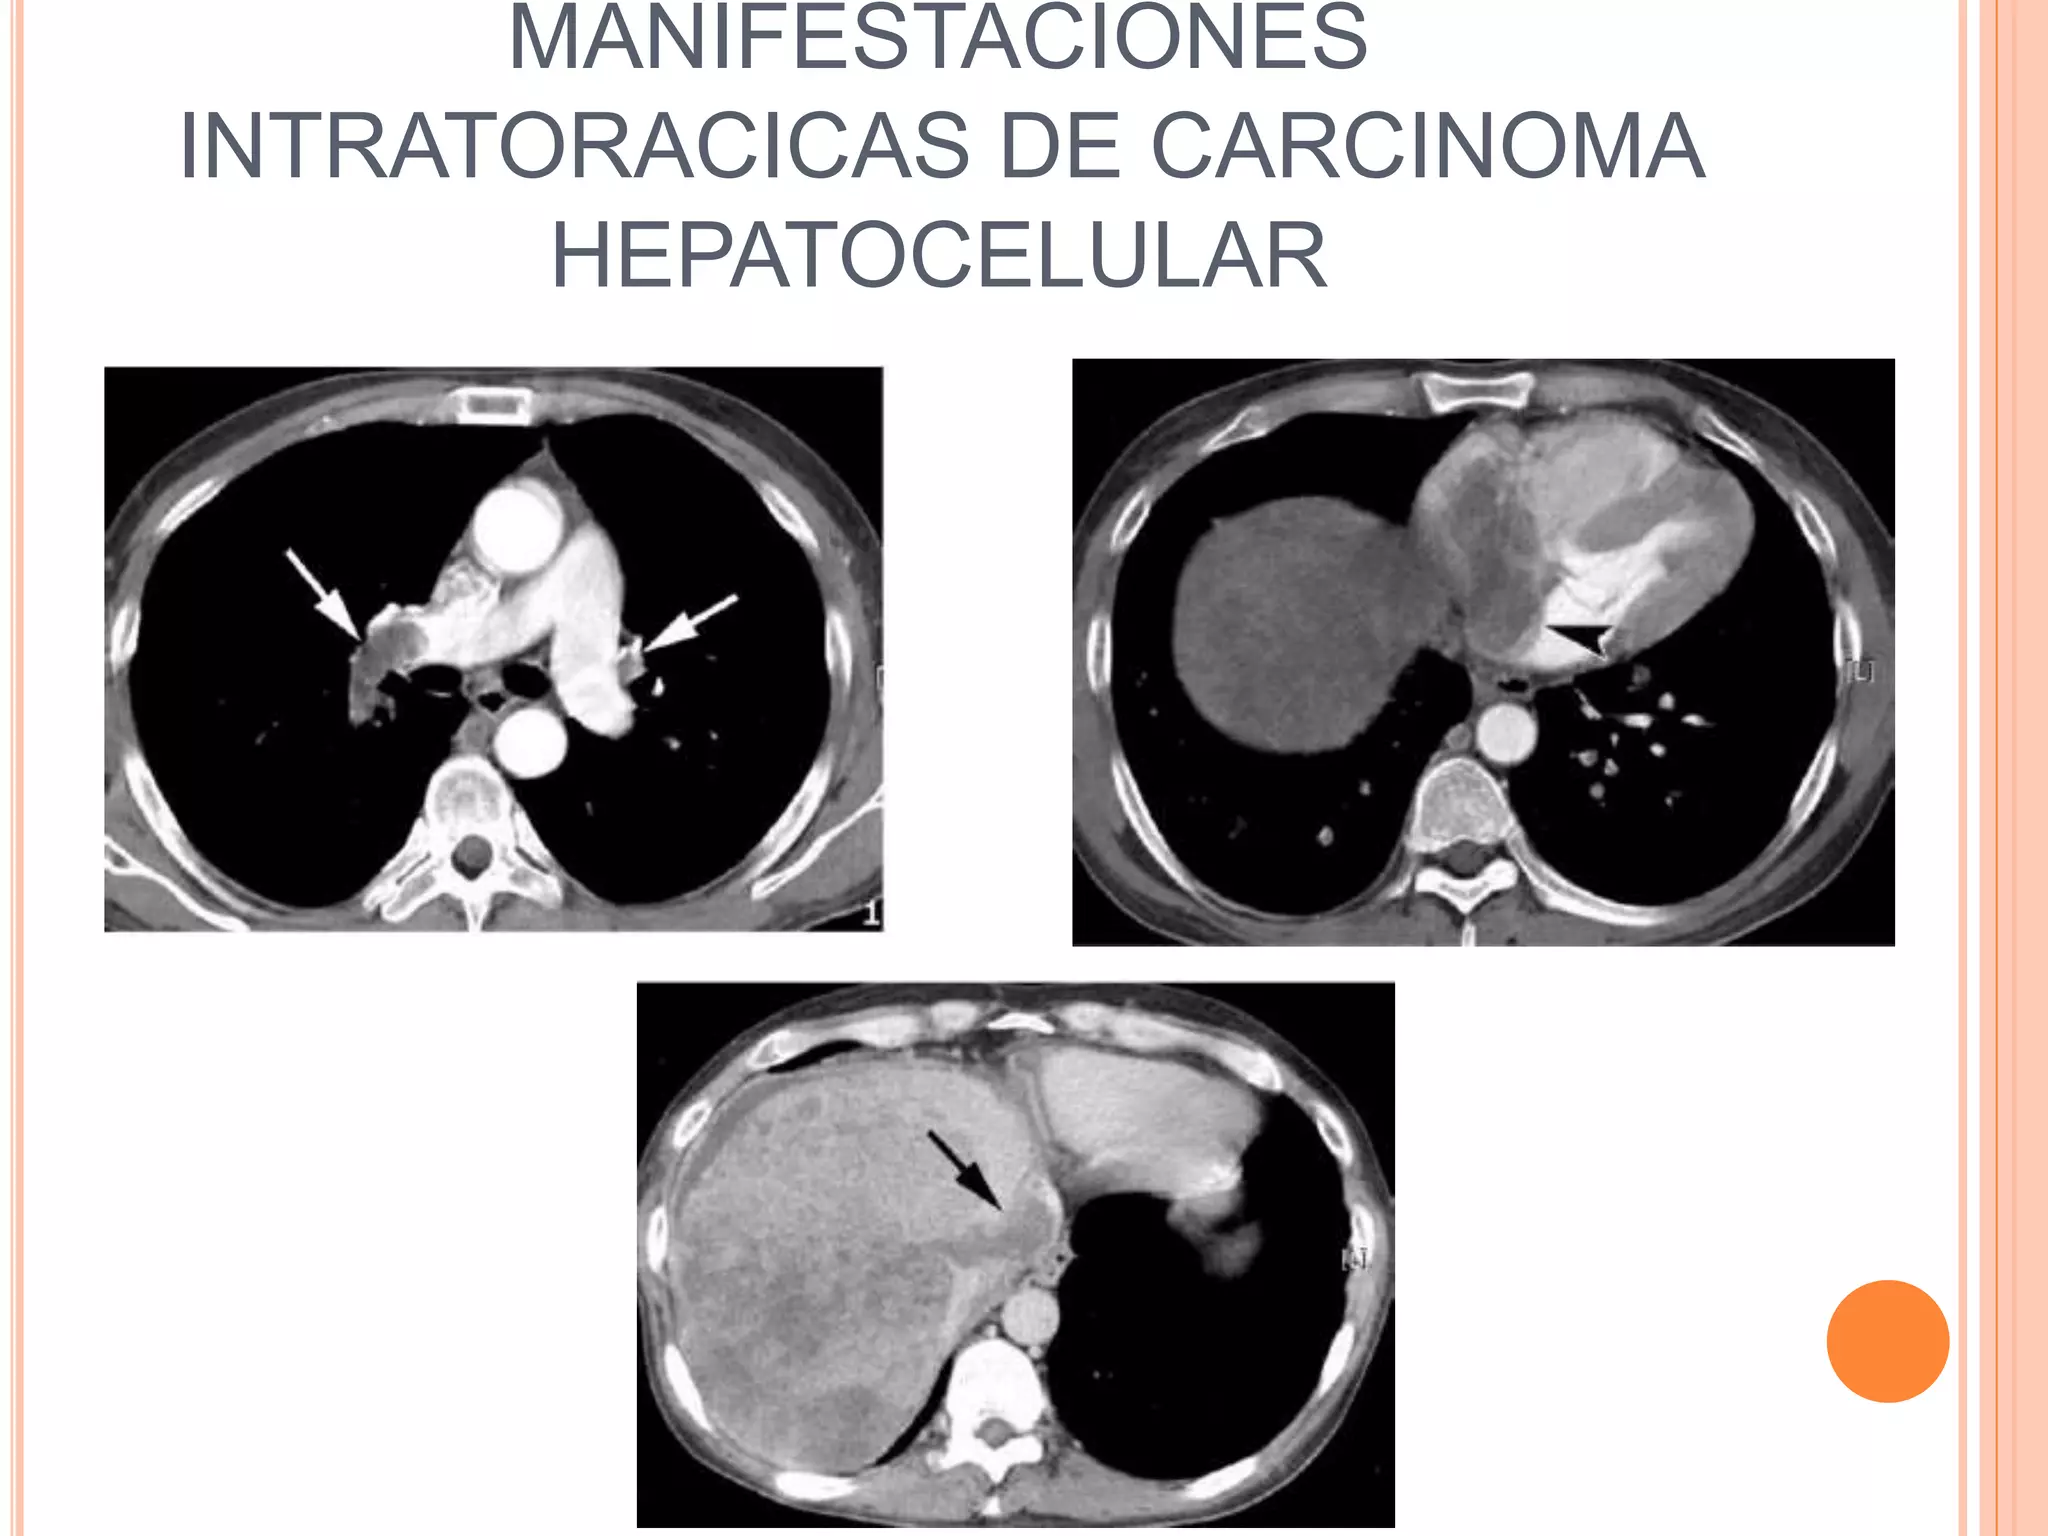

El documento aborda complicaciones torácicas en pacientes con cirrosis hepática, resaltando hallazgos radiológicos importantes como hipoxemia leve y afectaciones en la vasculatura pulmonar. Se discuten síndromes como el hepatopulmonar y la hipertensión porto-pulmonar, junto con sus implicaciones clínicas y radiológicas. Finalmente, se mencionan infecciones y manifestaciones intratorácicas asociadas a carcinoma hepatocelular, así como enfermedades pulmonares intersticiales inducidas por medicamentos.